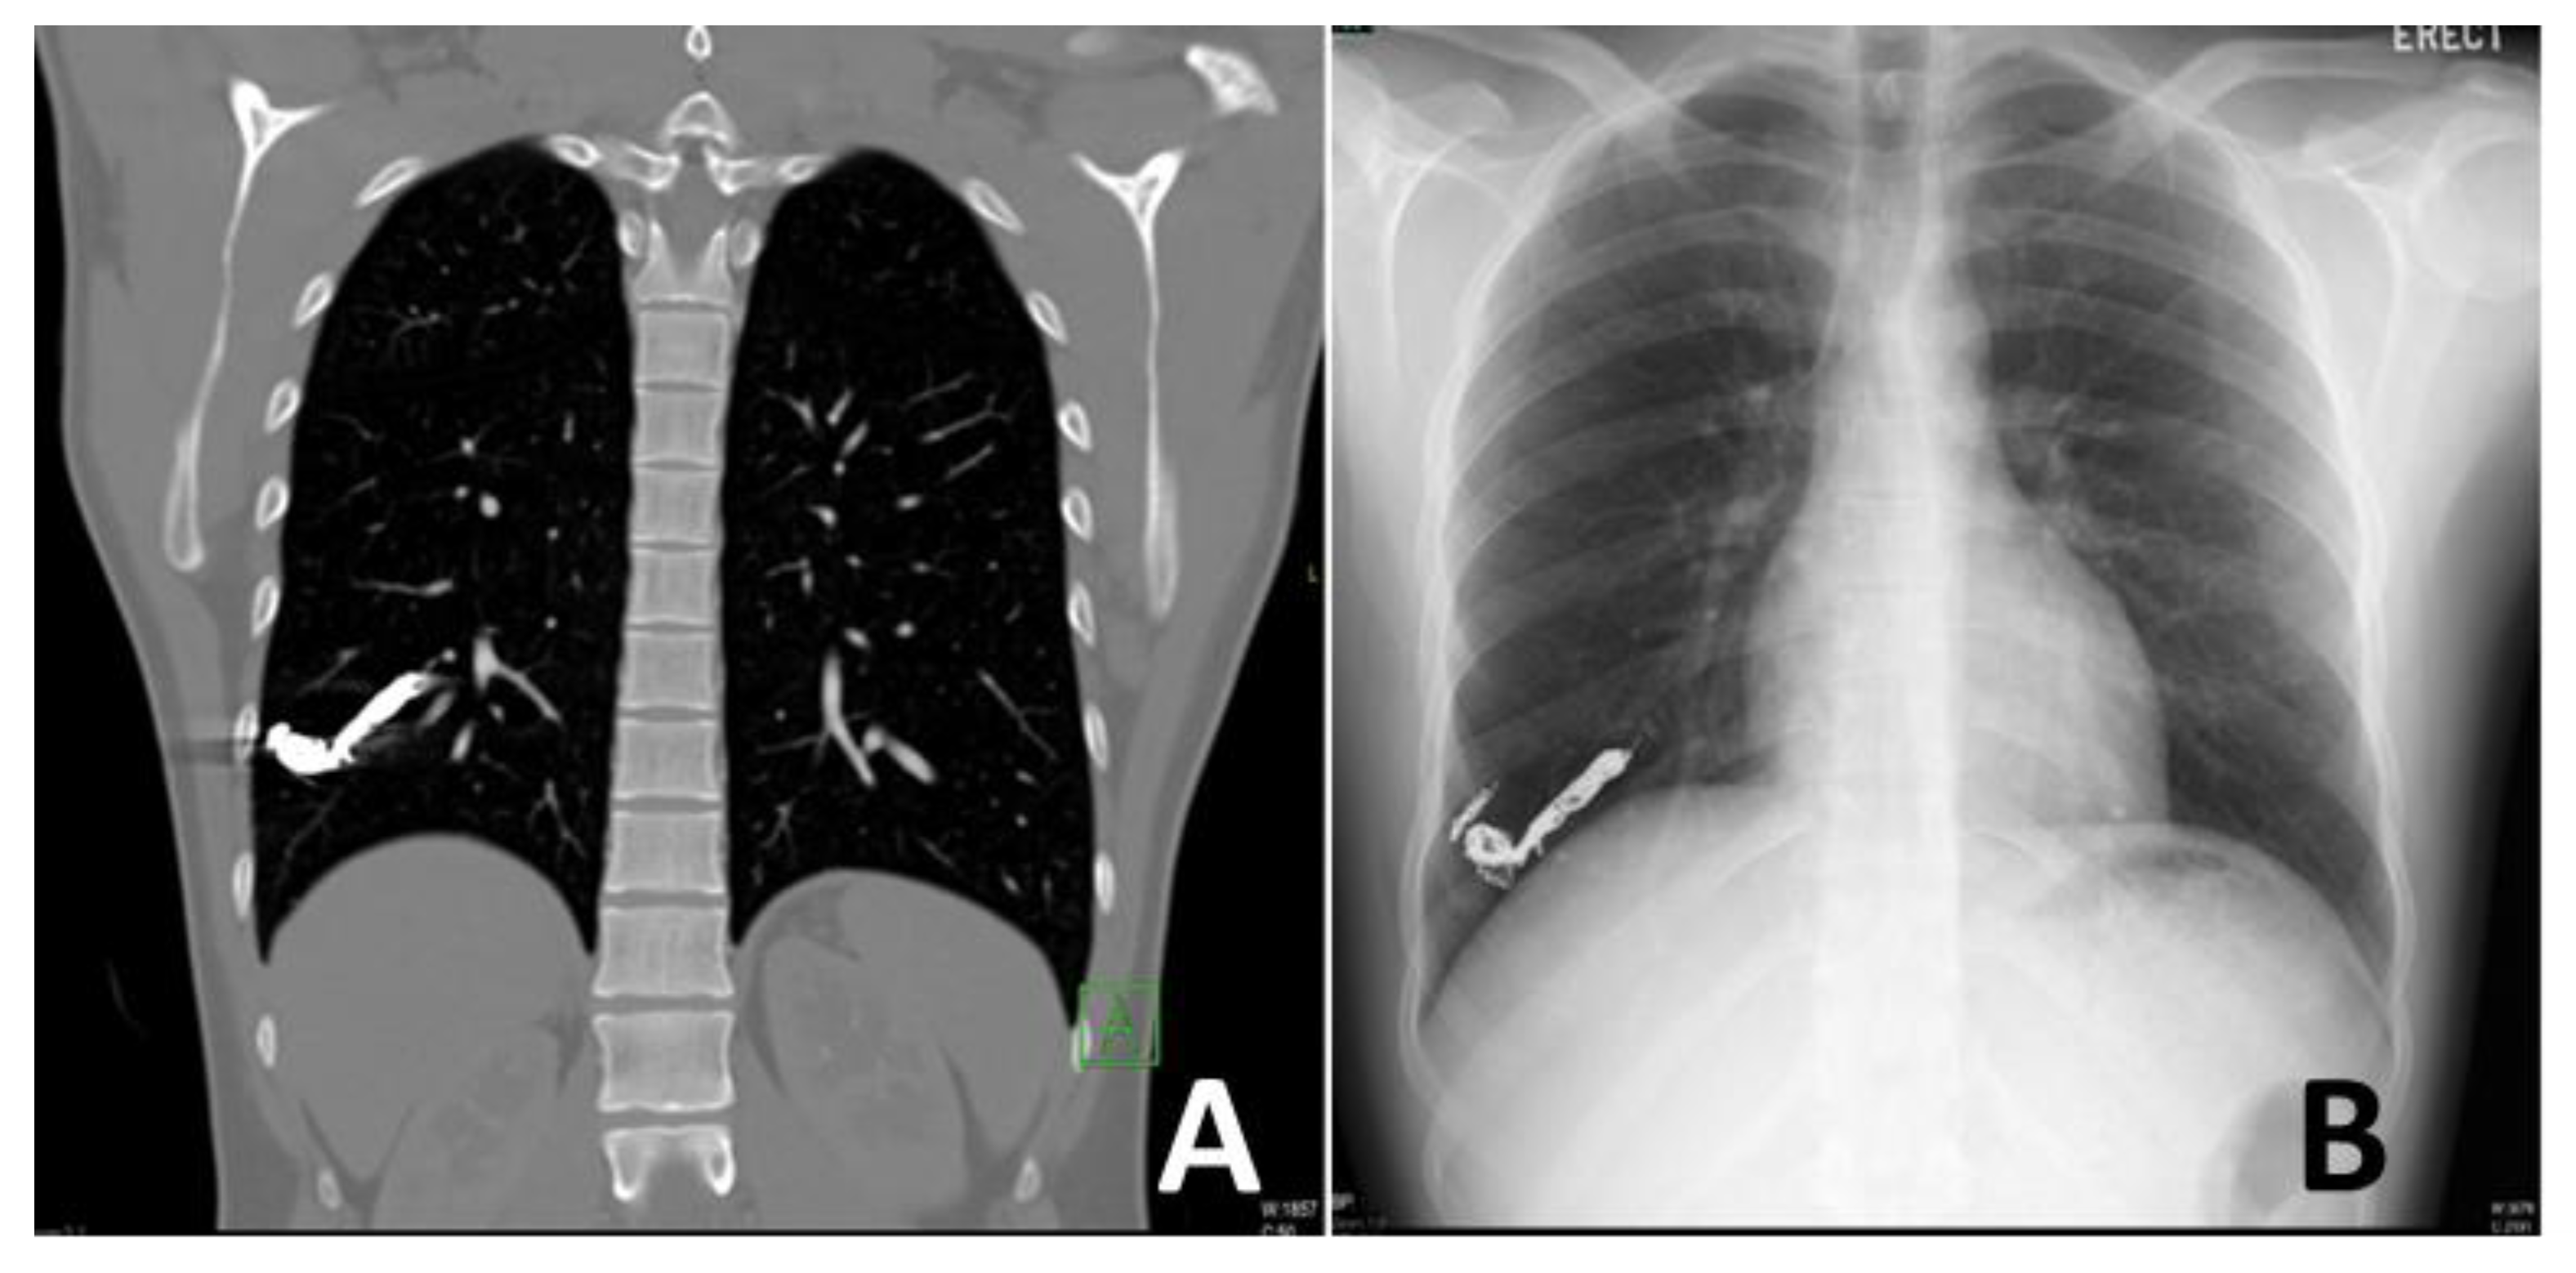

2. Radiological Diagnosis